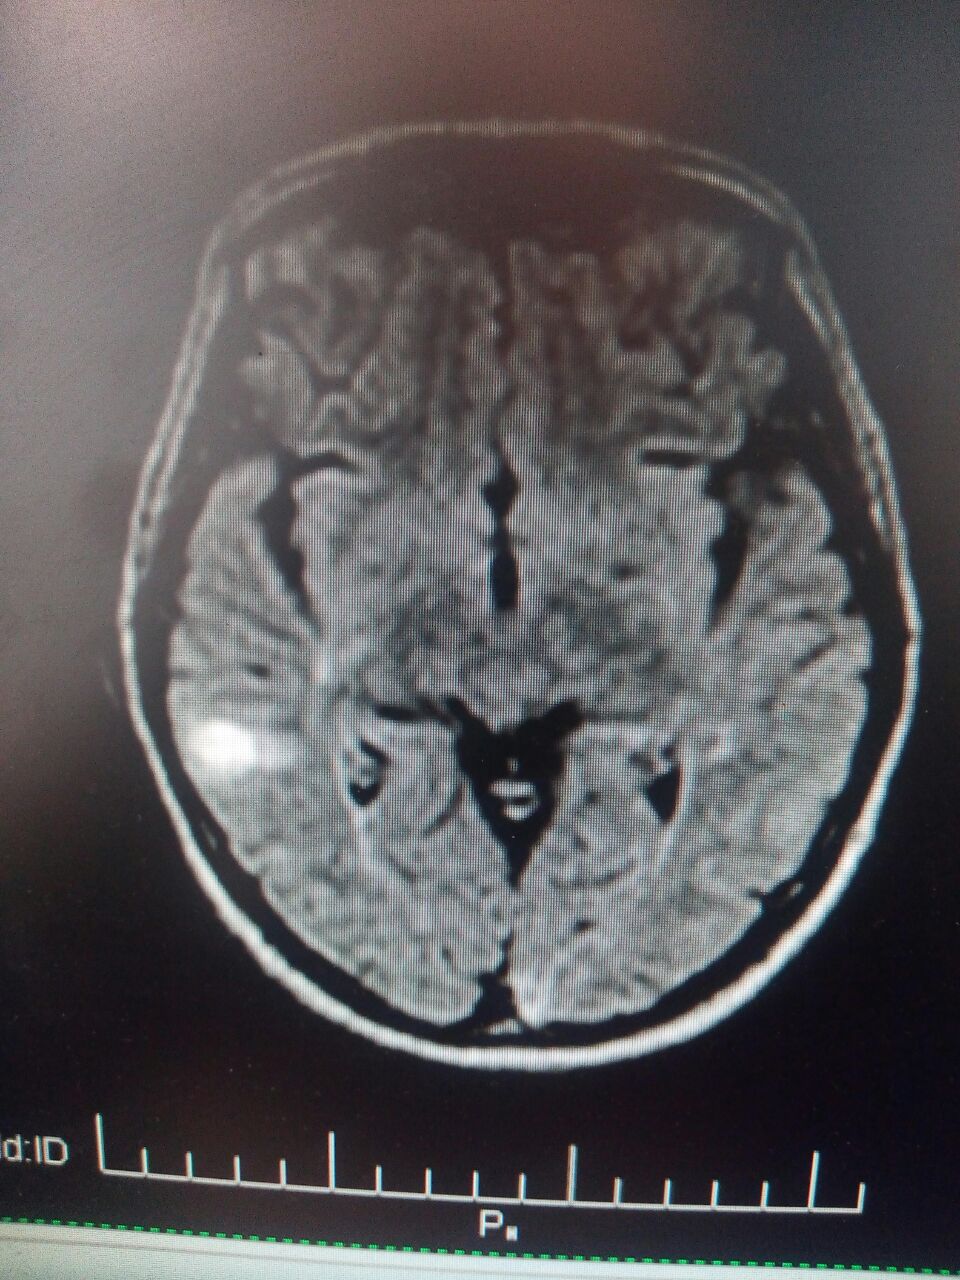

И что таки тут у нас?

Субкортикальная гематома правой височной доли.

Но это ещё не все.

Гематомы в паравентрикулярных отделах?

Nope

Кистозно-глиозные изменения